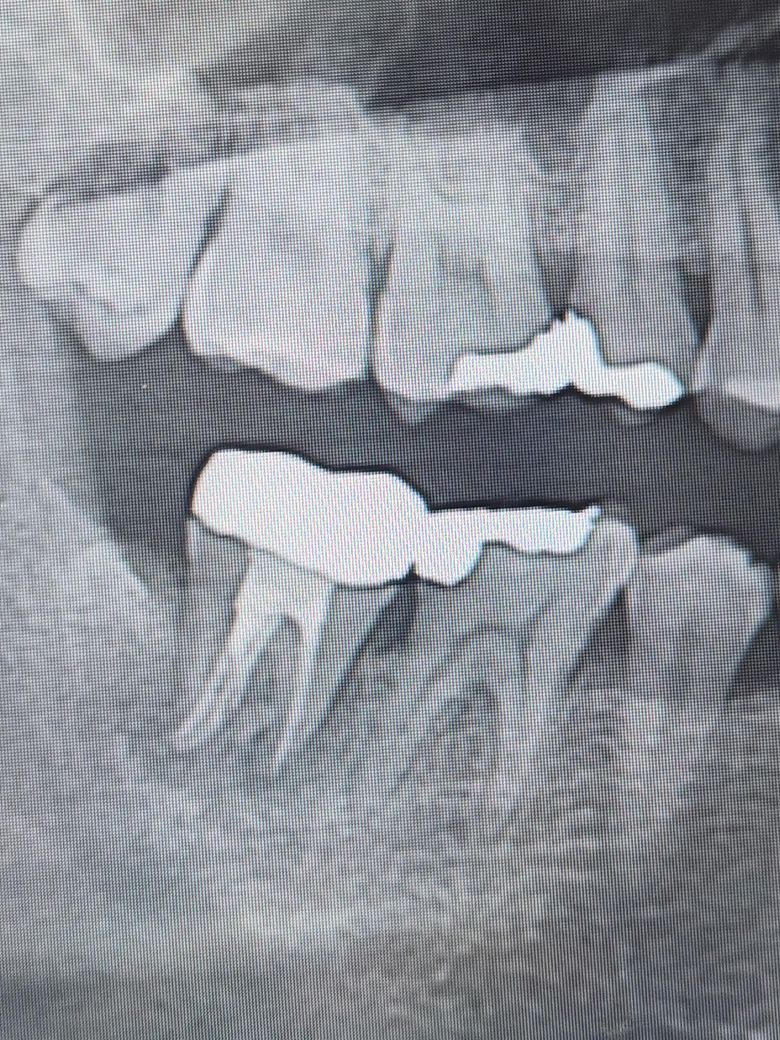

• 1번 째 사진

오른쪽 어금니의 경우 방사선상 치조골의 손실형태가 J자 형태를 보이는 전형적으로 치근파절이 생겼을때 보이는 증상입니다.

치아 뿌리에 금이 갔다면 결과적으로 발치를 하는 방법으로 치료를 하게 됩니다.

왼쪽아래 어금니의 경우에는 신경관 감염으로 인한 치근단 질환으로 재신경치료를 해서 염증을 줄이는것을 시도해 볼수 있을것으로 생각됩니다.